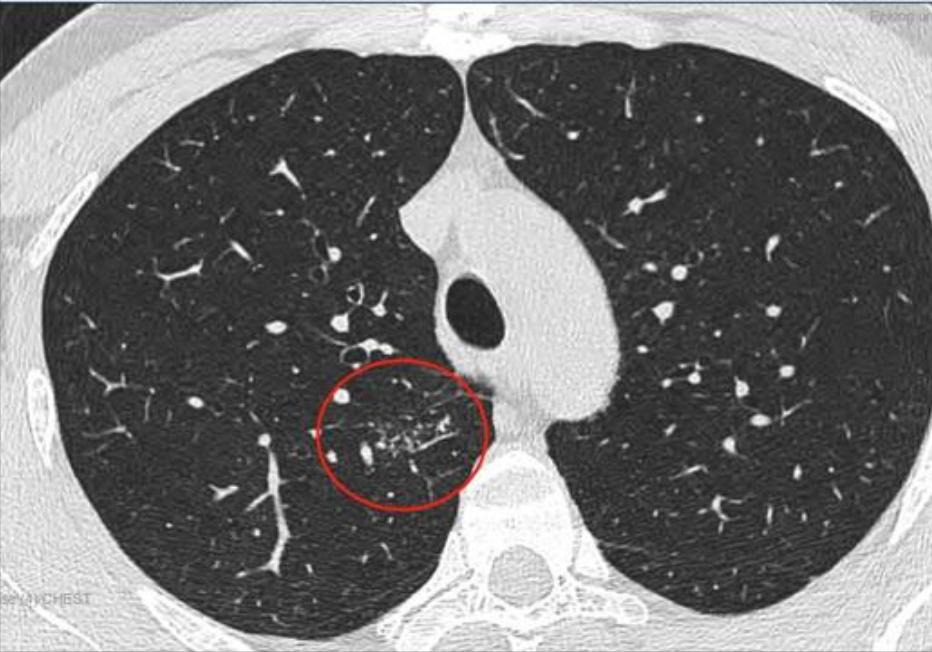

这是11月15日的CT图像与上次(7月29日)CT图像对比图:

再发一张:

辛苦主任,您看一下,结节虽然缩小了,还有1.7*0.9 CM,其他俩肺叶还有陈旧性病灶,应该继续服用拜复乐和夏枯草吗?8月份查过:男性肿标9项、过敏源检测(总IgE)、鳞状上皮细胞癌相关抗原、GM试验、隐球菌抗原、1,3-β-D葡聚糖 都是阴性,在正常范围内。就是结核感染T细胞还没查,您看是否需要查一下?主任辛苦您了,谢谢您!